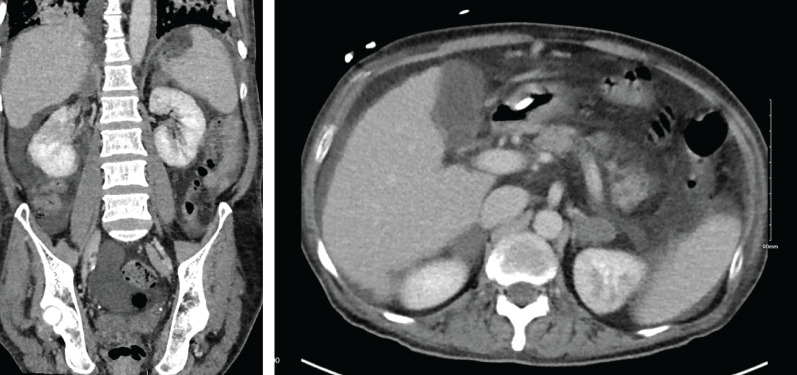

This is the first case report detailing co-infection with both PJP and disseminated histoplasmosis in a patient without HIV infection, and it highlights the immune-suppressive potential of poorly controlled diabetes and liver cirrhosis https://bit.ly/4dXUOX4.